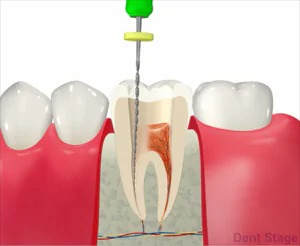

1ラバーダム防湿

歯に薄いゴムのシートをかけ、周囲を消毒します。これによりお口の中の唾液が治療中の根管内に入らないようにし、無菌的な治療を行います。(お口の中は細菌だらけなんです・・・)根の治療においてこのラバーダムは一番大事な処置です。これをする事によって文献上で成功率が上がるのが示されています。

ただ、状況によっては使用できない場合もあります。

3抜髄

炎症を起こしてしまった神経を抜いていきます。この時使用するのはファイルというヤスリのようなものを使用します。

5根管洗浄

内部の消毒を行います。一般的には次亜塩素酸水溶液を用います。当院では、より洗浄効果の高い次亜塩素酸水溶液とEDTA(根管内に詰まった切削片を溶かす)を交互に使い洗浄します。